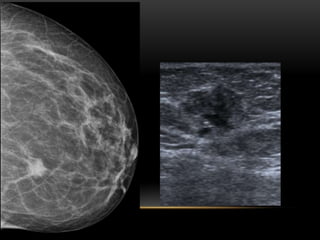

BIRADS 3

Semiología:

• Nódulo sólido único de forma redondeada, oval o lobulada, márgenes

circunscritos, densidad mamográfica igual al parénquima e

hipoecogénico en ecografía, con orientación paralela (eje vertical

menor que el transversal). Incluye nódulos con márgenes ocultos en

mamografía, siempre que se confirmen como circunscritos en

ecografía.

• Quiste complicado no palpable, quiste complejo y cumulo de

microquistes

• Microcalcificaciones puntiformes agrupadas.

• Asimetría focal NO PALPABLE.